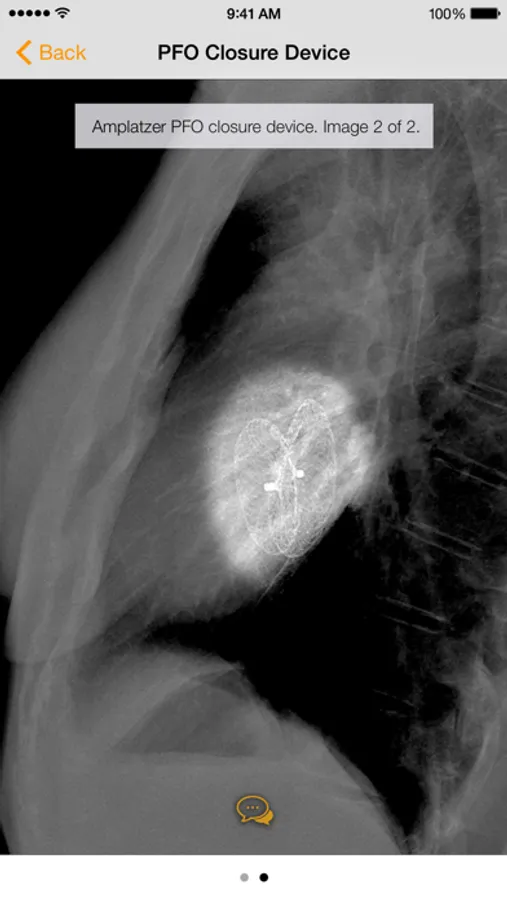

· Countless images, organized into the following categories: Common Cardiac Conduction Devices, Less Common Cardiac Conduction Devices, Vascular Devices, Airway Devices, Enteric Devices, Neurological Devices, Musculoskeletal Devices, and Miscellanenous Devices.

· Tap the caption icon to read more about the device and to see it highlighted on the chest radiograph.